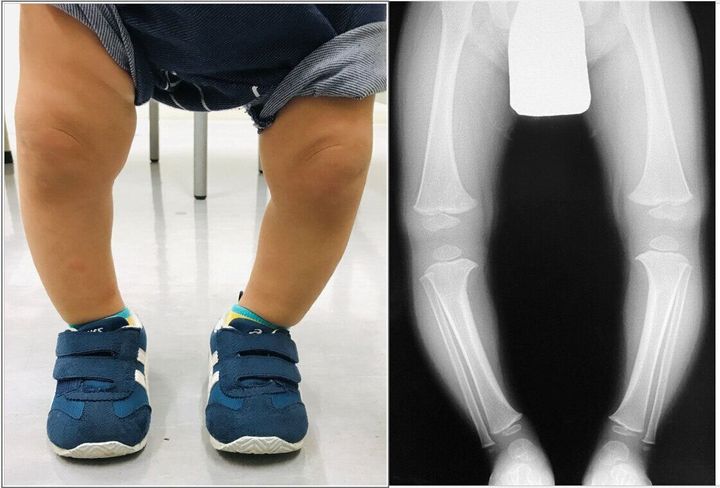

ほうっておいては治らない子も!乳幼児のO脚、産まれた環境にも原因が 専門家 たまひよ。